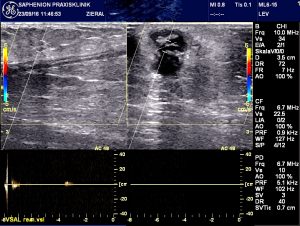

Sonographie nach simultaner VenaSeal® – Therapie der V. saphena magna und der Vena saphena akzessoria anterior

Sonography after simultaneous VenaSeal® – therapy of the great saphenous vein and the anterior saphenous vein